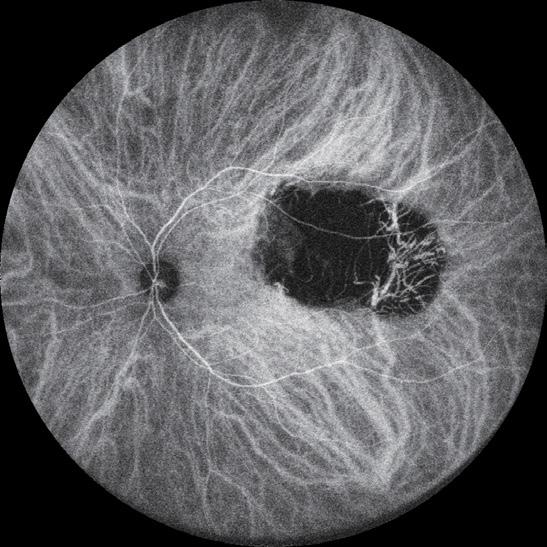

Post-paediatric cataract surgery Glaucoma: A: 3.5 years old child with cataract surgery done in infancy. Glaucoma with enlarged corneal diameter and a dislocated IOL are seen. One previous Ahmed glaucoma valve (AGV) in supero-temporal quadrant has failed to control IOP adequately; B: A second AGV plate is sutured in the infero-temporal quadrant. A closed chamber vertical translocation of haptics to glued IOL is then done sitting temporally, taking advantage of smaller vertical diameter of cornea; C: Adequate length of the externalised haptics of the IOL is seen; D: Haptics are tucked in. A well-centred IOL is seen. The AGV tube tip is positioned posterior to the iris in front of the IOL. Adequate vitrectomy is performed during IOL translocation as well as after inserting the tube tip